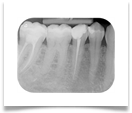

Nel nostro Studio impieghiamo un sistema radiografico computerizzato, il Vista Scan Plus della Dürr che consente di ottenere immagini di alta qualità (vedi confronto analogico/digitale) con dosi radiogene sensibilmente più basse per il paziente.

Con Vistascan Plus siamo in grado di ottenere, nel giro di pochi minuti, tutte le immagini che ci servono per un corretto ausilio diagnostico: bitewing, endorali, ortopantomografie, teleradiografie.